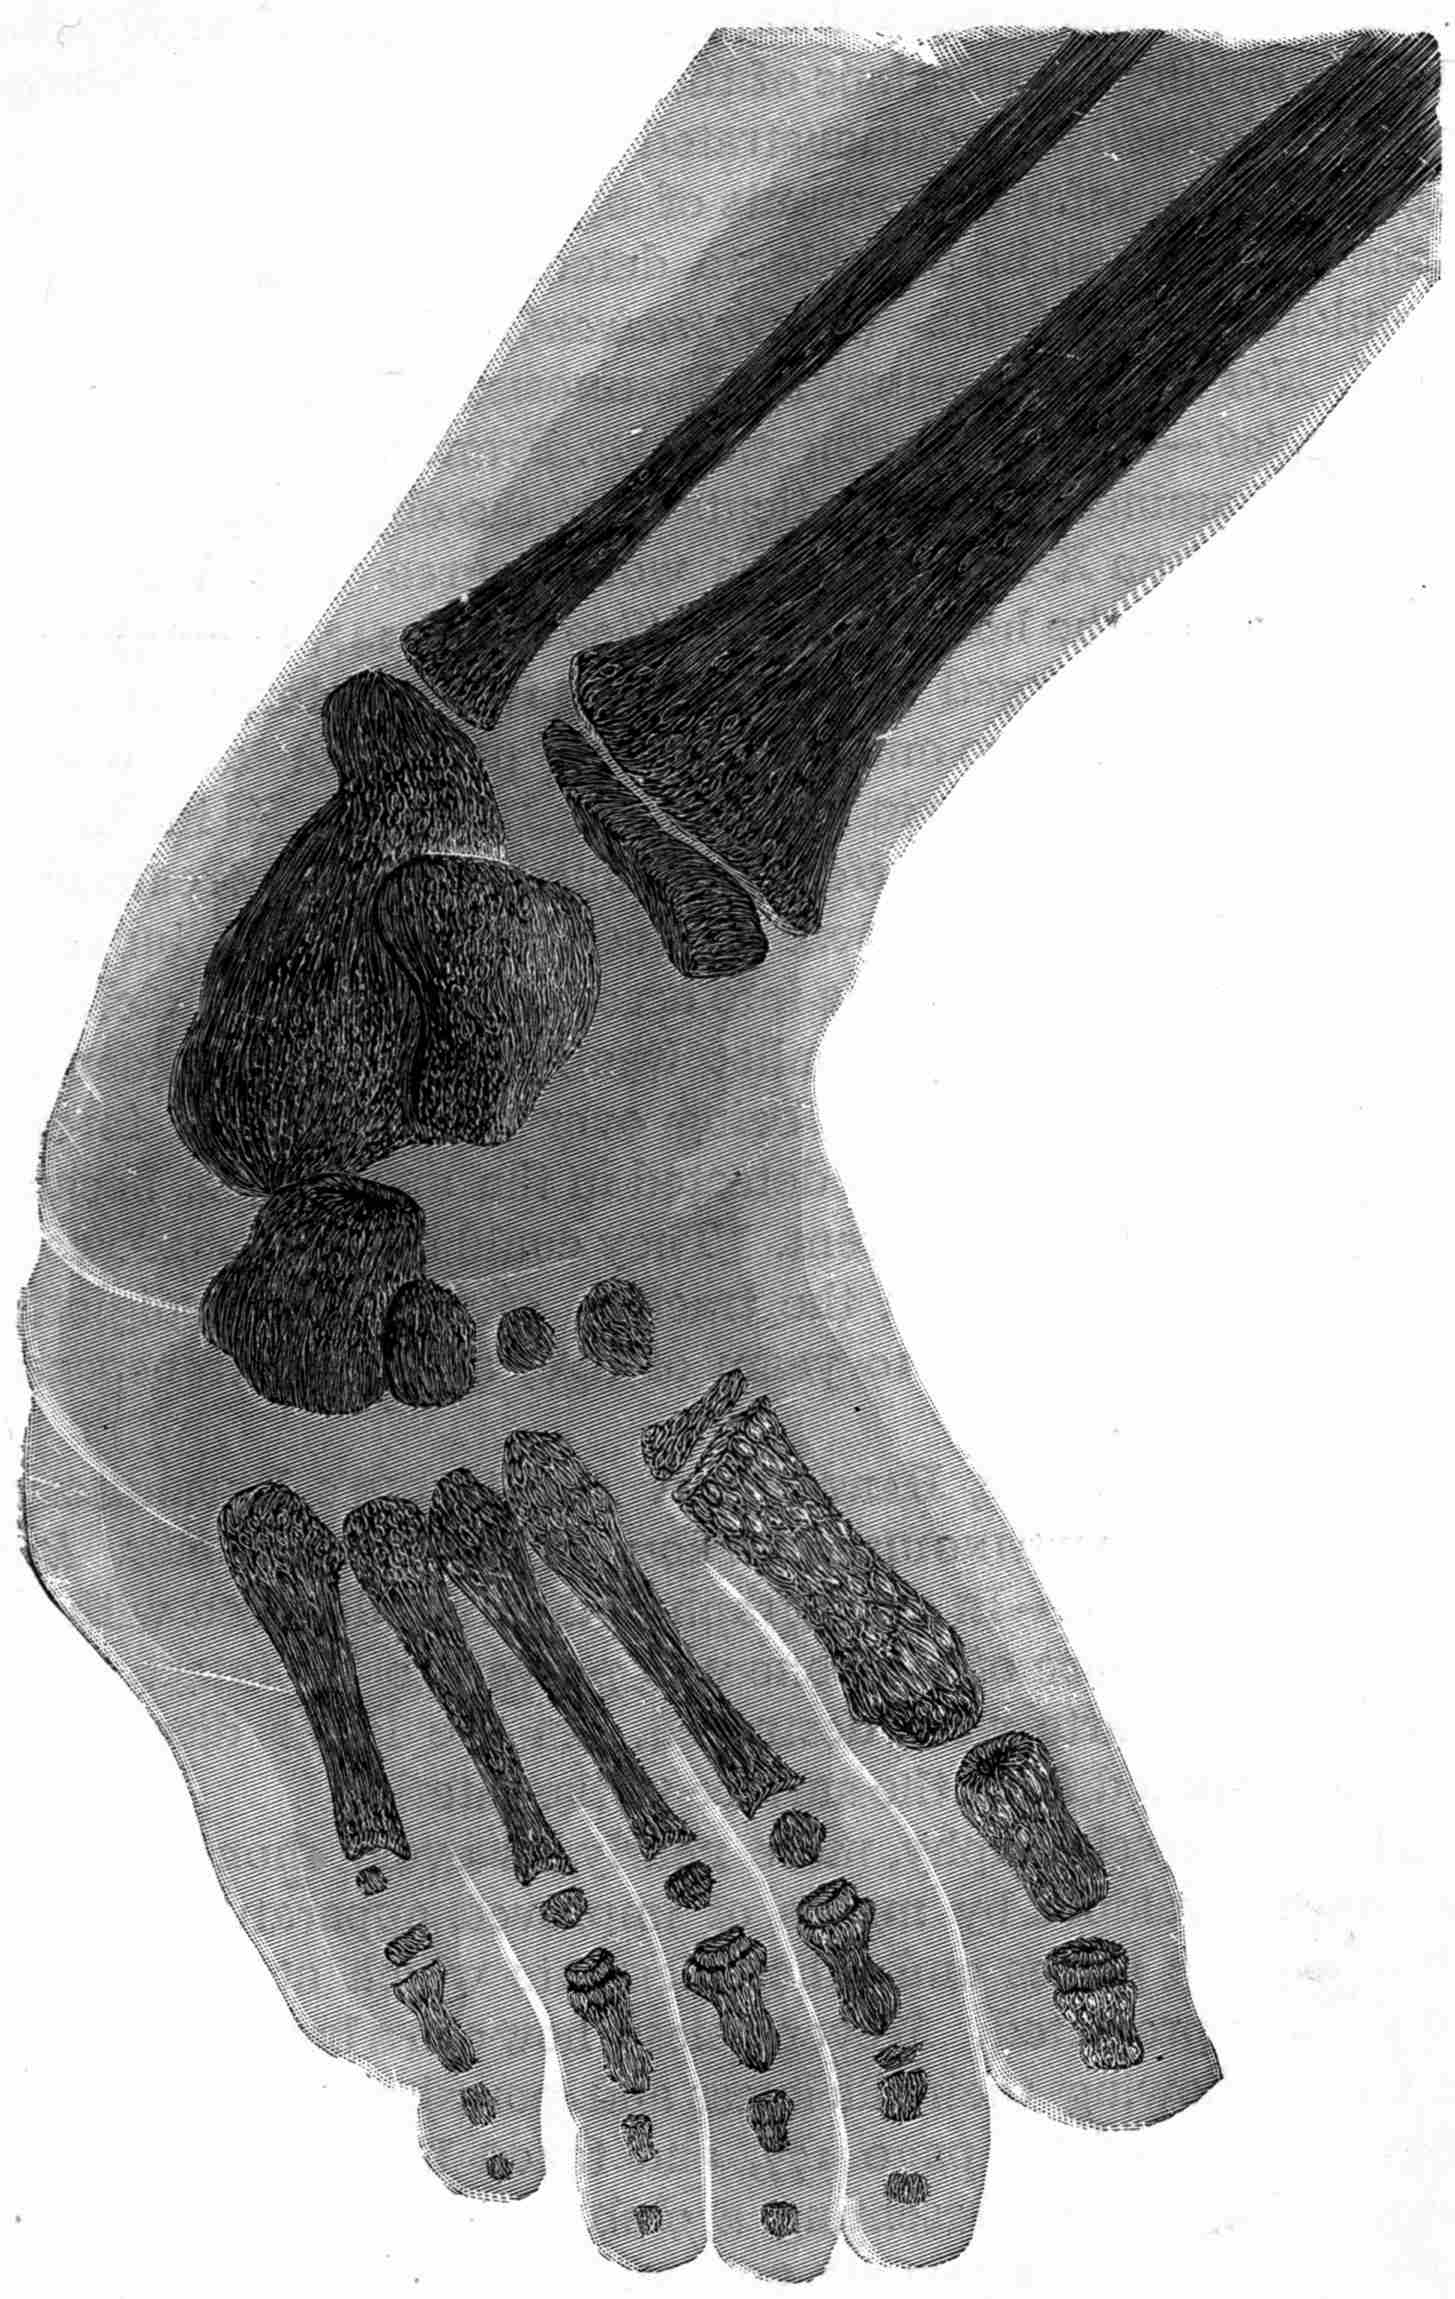

Fig. 1.—Head.

Fig. 2.—Broken Arm, Overlapping.

(Due to defective setting.)

Fig. 3.—Ribs.

Fig. 4.—Knee, Knickerbocker Buttons, Bullet in Femur.